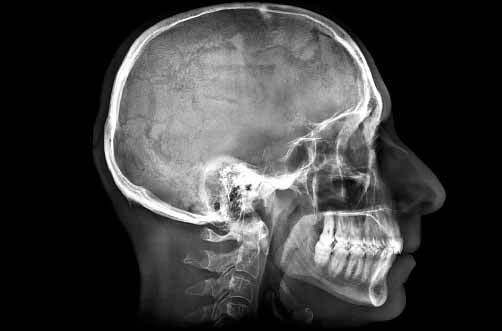

Craneo

El 8 de noviembre de 1895, Wilhelm Róntgen, al hacer pasar una corriente eléctrica de alto voltaje a través de un tubo vacío, observó fortuitamente, en unos cristales de sal de bario próximos, que éstos resplandecían con brillo fluorescente. Colocó su mano entre el tubo y las sales, y vio que aquélla, con la silueta de los huesos de sus dedos, proyectaba su sombra sobre las sales.

22 de Diciembre de 1898, Roentgen le realiza una radiografía a la mano de su esposa.